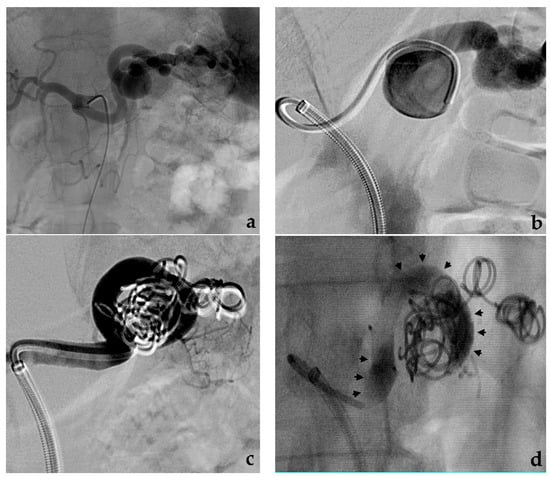

- Yasumoto, T.; Osuga, K.; Yamamoto, H.; Ono, Y.; Masada, M.; Mikami, K.; Kanamori, D.; Nakamura, M.; Tanaka, K.; Nakazawa, T.; et al. Long-term outcomes of coil packing for visceral aneurysms: Correlation between packing density and incidence of coil compaction or recanalization. J. Vasc. Interv. Radiol. 2013, 24, 1798–1807. [Google Scholar] [CrossRef] [PubMed]

- Wojtaszek, M.; Lamparski, K.; Wnuk, E.; Ostrowski, T.; Maciąg, R.; Rix, T.; Maj, E.; Milczarek, K.; Korzeniowski, K.; Rowiński, O. Selective occlusion of splenic artery aneurysms with the coil packing technique: The impact of packing density on aneurysm reperfusion correlated between contrast-enhanced MR angiography and digital subtraction angiography. Radiol. Med. 2019, 124, 450–459. [Google Scholar] [CrossRef]

- Venturini, M.; Marra, P.; Augello, L.; Colarieti, A.; Guazzarotti, G.; Palumbo, D.; Lanza, C.; Melissano, G.; Chiesa, R.; De Cobelli, F. Elective embolization of splenic artery aneurysms with an ethylene vinyl alcohol copolymer agent (Squid) and detachable coils. J. Vasc. Interv. Radiol. 2020, 31, 1110–1117. [Google Scholar] [CrossRef] [PubMed]